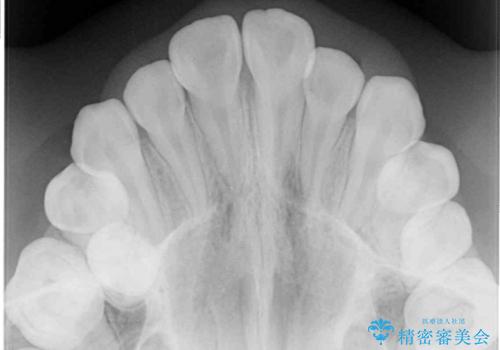

- 急速拡大装置・インビザライン

上顎骨の幅が下顎骨よりも小さいので、拡大装置により骨幅を広げて上下関係を改善し、その後インビザラインにて歯並びを整えることとしました。

上下の骨幅を改善したことで、スムーズに歯列矯正を行うことができました。